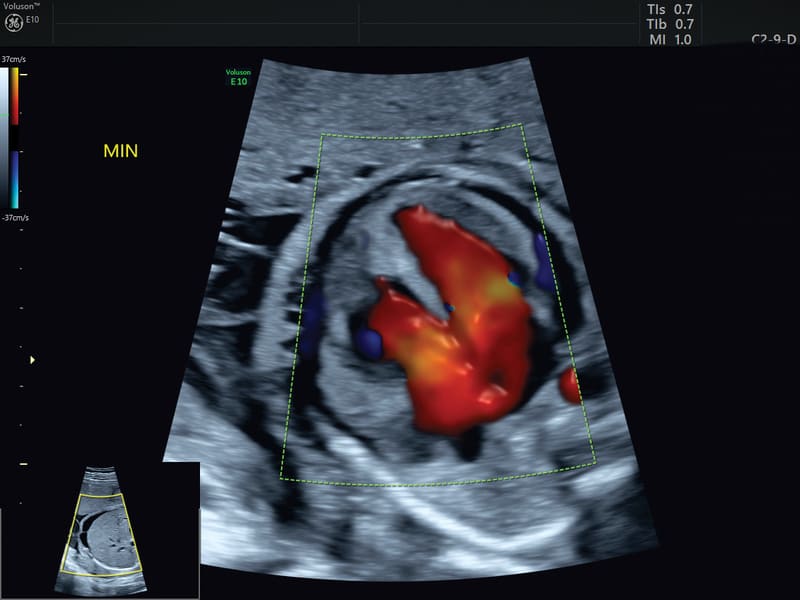

HDlive™ Flow e HDlive™ Flow Silhouette: Applica tutte le caratteristiche presenti in HDlive™ e HDlive™ Silhouette al rendering con campionamento di flusso volumetrico Color Doppler, Power e HDFlow™.

STIC: Per l’acquisizione 3D del cuore fetale, viene applicato un sofisticato algoritmo per la gestione e soppressione della distorsione causata dal movimento dei tessuti materni e fetali. Le immagini tomografiche sono riorganizzate in base alla fase del ciclo cardiaco e il data set 3D viene generato con solo immagini tomografiche nella stessa fase di ciclo cardiaco.

SonoVCAD Heart: strumento avanzato, basato sulla tecnologia Volume Ultrasound, CHE aiuta nella visualizzazione automatica delle scansione degli outflow cardiaci partendo dal volume data set acquisito. Permette una ricostruzione completa e automatizzata, relativa all’esame cardio fetale seguendo le linee guida delle società scientifiche AIUM, ACOG, ACR e ISUOG.

Semplicemente con due click il sistema è in grado di effettuare l’analisi e proporre le principali proiezioni.